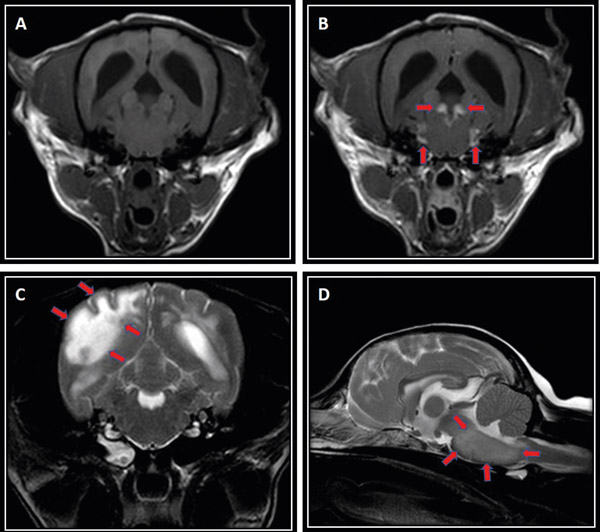

Diagnosis: Diagnosis is made based on a combination of signalment, clinical examination, MRI and CSF analysis. MUA is considered ultimately a fatal condition without treatment and so should be considered as an important differential diagnosis for any young-middle aged small breed dog with acute and progressive central neurological signs. MRI often shows multi-focal asymmetrical poorly demarcated intra-axial lesions that may affect the cerebrum, brainstem and/or cerebellum, with varying degrees of contrast enhancement (see Figure 2). These lesions may produce mass effect or in severe cases herniation of brain tissue due to raised intra-cranial pressure. In cases with clinical or radiological concerns of raised ICP, CSF collection is contraindicated. CSF typically shows a marked elevation in total nucleated cell count (TNCC; reference < five white blood cells /μL) and total protein (TP; reference <0.25 mg/dL), with a mononuclear pleocytosis. In one study, four inclusion criteria for diagnosis were described: dogs older than 6 months of age; multiple, single or diffuse intra-axial hyperintensities on T2-weighted (T2W) MR images; pleocytosis on CSF analysis with >50 per cent of monocytes/lymphocytes; and lastly, exclusion of infectious diseases.

Figure 2: MRI sequences of dogs diagnosed with MUA; T1-weighted transverse image at the level of the pons pre-(A) and post-gadolinium (B) contrast administration. Note the bilateral marked contrast enhancement and thickening of the meninges at this level (red arrows). In another dog with suspected NLE (C), marked asymmetrical T2-weighted hyperintensity is seen on transverse sequence, most predominantly affecting the occipital lobe with loss of white/grey matter distinction (red arrows). The brainstem may also be affected as seen in another dog (D) with diffuse ill-defined T2-weighted hyperintensity and generalised swelling seen on sagittal sequence (red arrows).